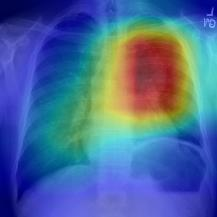

Thoracic disease detection from chest radiographs using deep learning methods has been an active area of research in the last decade. Most previous methods attempt to focus on the diseased organs of the image by identifying spatial regions responsible for significant contributions to the model's prediction. In contrast, expert radiologists first locate the prominent anatomical structures before determining if those regions are anomalous. Therefore, integrating anatomical knowledge within deep learning models could bring substantial improvement in automatic disease classification. This work proposes an anatomy-aware attention-based architecture named Anatomy X-Net, that prioritizes the spatial features guided by the pre-identified anatomy regions. We leverage a semi-supervised learning method using the JSRT dataset containing organ-level annotation to obtain the anatomical segmentation masks (for lungs and heart) for the NIH and CheXpert datasets. The proposed Anatomy X-Net uses the pre-trained DenseNet-121 as the backbone network with two corresponding structured modules, the Anatomy Aware Attention (AAA) and Probabilistic Weighted Average Pooling (PWAP), in a cohesive framework for anatomical attention learning. Our proposed method sets new state-of-the-art performance on the official NIH test set with an AUC score of 0.8439, proving the efficacy of utilizing the anatomy segmentation knowledge to improve the thoracic disease classification. Furthermore, the Anatomy X-Net yields an averaged AUC of 0.9020 on the Stanford CheXpert dataset, improving on existing methods that demonstrate the generalizability of the proposed framework.